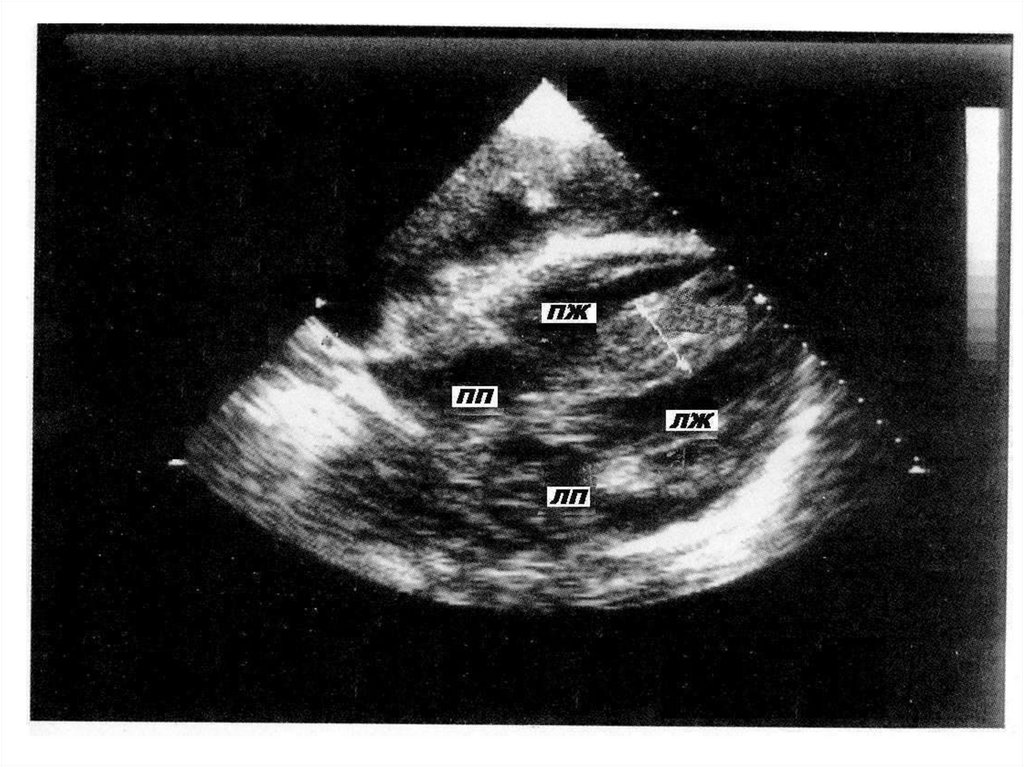

НЕКОМПАКТНЫЙ МИОКАРД

Некомпактный (губчатый) миокард левого желудочка

(НМЛЖ) является следствием нарушения развития

миокарда в процессе эмбрионального развития.

Основной признак этого заболевания – глубокие трабекулы

в миокарде левого желудочка и межжелудочковой

перегородке, что влечет за собой снижение систолической

функции левого желудочка.

В части случаев в патологический процесс может

вовлекаться миокард правого желудочка.

КЛИНИЧЕСКИЕ ПРОЯВЛЕНИЯ НЕКОМПАКТНОГО

МИОКАРДА

Заболевание проявляется постепенным нарастанием

симптомов сердечной недостаточности, желудочковыми

нарушениями сердечного ритма и проводимости.

Также возможно формирование тромбов в области

трабекул с развитием тромбоэмболических

осложнений.